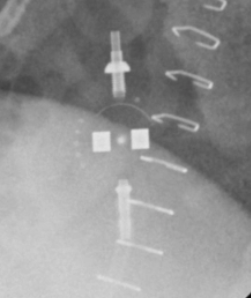

Medtronic Strata NSC

Medtronic Strata NSC valves are adjustable csf shunt valves.